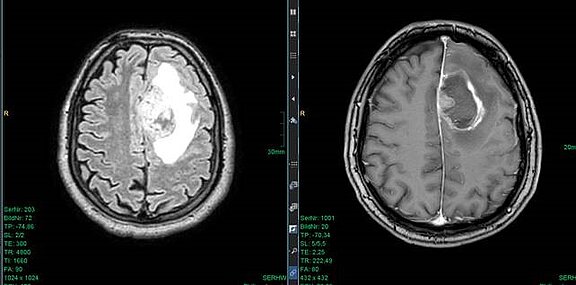

Operative Entfernung von Hirntumoren

Oft müssen Hirntumore operativ entfernt werden. Sowohl um die Diagnose als auch die Operation kümmert sich die Neurochirurgie.

Neben der Entfernung des Hirntumors ist die Erhaltung aller Gehirnfunktionen Ziel der Operation. Dies schaffen wir durch modernste elektrophysiologische und präoperative Mappingmethoden. Das erfordert viel Umsicht in der Diagnose, weswegen wir vorweg verschiedene Untersuchungen durchführen. Beispielsweise helfen bildgebende Verfahren, Lage und Größe des Tumors genauestens zu bestimmen. Auch die aktuelle Gesundheit und das Alter der Patientinnen und Patienten werden beachtet.